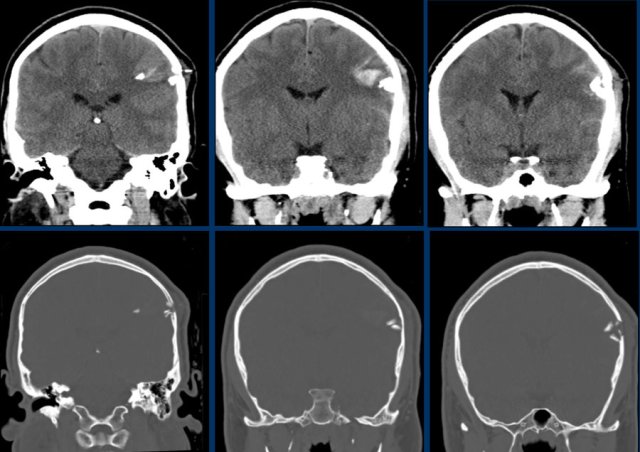

A subdural hematoma can spread along the falx and tentorium as seen in this case.

This is another coupe contrecoupe type of injury with contusional hemorrhages and a subdural hematoma in the left frontal lobe near the skull base (red arrow).

There is a subarachnoid hemorrhage on the right with a fracture of the parietal bone (yellow arrow).